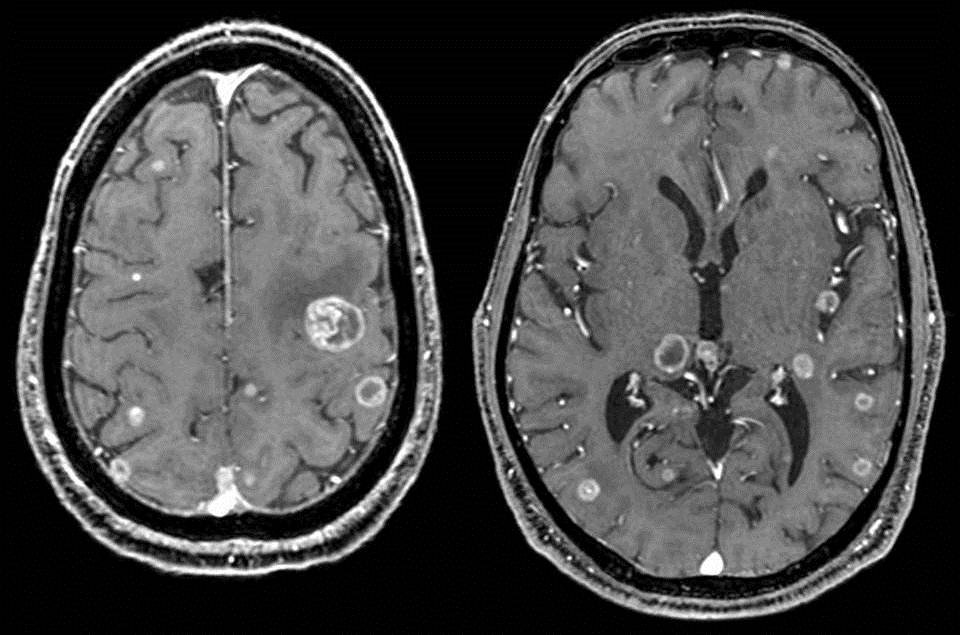

- Bệnh liên quan đến Não bộ như u não, tai biến mạch máu não, u dây thần kinh sọ não, các bệnh thoái hóa não, các dị dạng bẩm sinh của não, động kinh, tự kỷ, các Chấn thương sọ não có lâm sàng không giải thích đầy đủ trên CT...

- Các bệnh ung thư hoặc tầm soát ung thư (MRI toàn thân)

Kỹ thuật chụp cộng hưởng từ MRI có thể góp phần phát hiện sớm nhiều căn bệnh nguy hiểm nên được các bác sĩ chuyên gia đánh giá cao, kỹ thuật này có những ưu điểm nổi bật như:

Có khả năng đánh giá tốt tình trạng của những tổn thương rất nhỏ trong cơ thể như mạch máu, thần kinh...